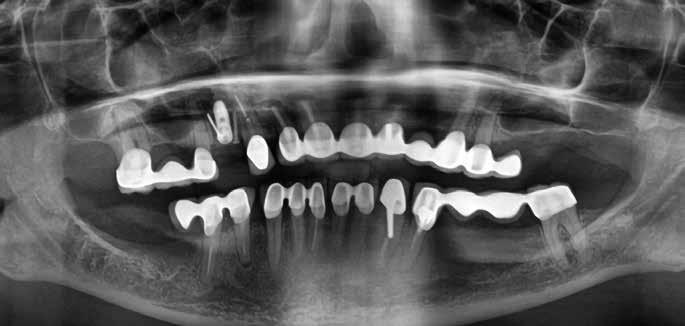

A műtéti tervezéshez mindkét esetben CBCT-felvételt használtunk, majd az utánkövetési időszakban periapikális röntgenfelvételekkel ellenőriztük az implantátumokat. A fogeltávolítást követően azonnali implantáció történt, az alveolus fala és az implantátum felszíne közt fennmaradó réseket csontpótlóval töltöttük ki. A három hónapos gyógyulás leteltével az ideiglenes koronákat eltávolítottuk, A-szilikonnal lenyomatot vettünk, majd három lítium-diszilikát és egy monolitikus cirkónium-dioxid korona készült. A páciensek utánkövetése mindkét esetben minimum tizenkét hónap volt, amelynek során valamennyi implantátumot klinikailag és radiológiailag is sikeresnek ítéltünk az osszeointegráció, a marginális csont stabilitása és a periimplantáris szövetek egészsége tekintetében.

A végleges ragasztást követően röntgenfelvételt készítettünk, amelyet összevetettünk a közvetlenül a műtét után készült felvételekkel: a marginális csontszint változatlan volt. A pácienseket 14 hónapon keresztül rendszeresen visszahívtuk. Klinikai és röntgenvizsgálattal sem tapasztaltunk komplikációt (12. a–b ábrák)

lantátum 4,3 mm átmérőjű és 13 mm hosszúságú volt. A behajtási nyomaték mind a négy esetben 35–40 Ncm tartományban volt, amely lehetővé tette az azonnali terhelést. Tizenkét hónap elteltével egyik implantátumnál sem tapasztaltunk csontfelszívódást, a kemény- és a lágyszövetek stabilitása kielégítő volt.

Tanulmányunk célja összesen négy, rágó területre beültetett kétrészes Zi ceramic implant® kerámiaimplantátum (Neodent) teljesítményének értékelése volt. A legalább tizenkét hónapos utánkövetés alatt egyetlen esetben sem tapasztaltunk technikai vagy biológiai szövődményt, amely bizonyítja az implantátum osszeointegrációjának klinikai és radiológiai sikerét, valamint a lágy- és keményszövetek volumenének stabilitását. Eredményeink összhangban vannak más, azonos implantátumokkal és hasonló utánkövetési periódussal készült tanulmányok tapasztalataival [8, 10]. Korábbi, állatokon végzett vizsgálatok kimutatták, hogy a cirkónium-dioxid implantátumok osszeointegrációja megbízható és biztonságos, még különböző terhelési viszonyok mellett is [11, 12]. Mint azt korábban említettük, jelen tanulmányban mind a négy implantátum sikeresen osszeointegrálódott a vizsgált tizenkét hónap alatt.

Medentika® ÉLETHOSSZIG TARTÓ GARANCIA

Korábbi tanulmányok kimutatták, hogy a cirkónium-dioxid felületek hajlama a biofilmképződésre kisebb, mint a titánfelületeké [13]. Jelen vizsgálatban gyulladásos folyamatoktól mentes és egészséges megjelenésű periimplantáris szöveteket lehetett megfigyelni (12. a–b ábra). Egy másik, a jelen tanulmányban alkalmazott implantátumrendszerrel végzett prospektív klinikai vizsgálat kimutatta, hogy legalább tizenkét hónapos utánkövetés mellett sem volt tapasztalható kóros elváltozás a periimplantáris lágyszövetekben [8]. Ugyanez a tanulmány, egy további prospektív klinikai vizsgálat, valamint saját eredményeink egybehangzóan azt mutatják, hogy a marginális csont szintje a megfigyelt idő alatt stabil volt [8, 10, 14]. Az itt bemutatott két páciens kerámiaimplantátumokat kapott a felső moláris régióba. Komplikációkat, mint például az implantátum vagy a felépítmény törése, nem tapasztaltunk. Ez a tény megerősíti más tanulmányok megállapításait is, amelyek szerint a kerámia fogászati implantátumok gyártására az ittriummal stabilizált cirkónium-dioxid (YTZP) a legalkalmasabb. Az YTZP esztétikai és biológiai előnyei mellett a korrózióval, kopással és rágóerőkkel szembeni nagyfokú ellenálló képessége is kimagasló [15]. Érdemes megemlíteni, hogy jelen tanulmány tizenkét hónapos követési időszakot ölel fel, amely rövidnek számít. Azonban ezen időszak alatt nem tapasztaltunk klinikai vagy biológiai szövődményt, külö-

10. a ábra: Végleges lítium-diszilikát koronák. – 10. b ábra: Végleges monolitikus cirkónium-dioxid korona. – 11. a–b ábrák: Klinikai megjelenés tizenkét hónap elteltével. 12. a–b ábrák: Tizenkét hónapos kontrollröntgen-felvételek.

Figyelembe véve az itt bemutatott esetek korlátait, tizenkét hónapos utánkövetés eredményei alapján az alkalmazott kétrészes cirkónium-dioxid implantátumrendszer biztonságos és megbízható alternatívát jelent a moláris fogak rehabilitációjában. Megállapításaink alátámasztására további vizsgálatokra van szükség, az itt bemutatott eseteket továbbra is figyelemmel kísérjük.